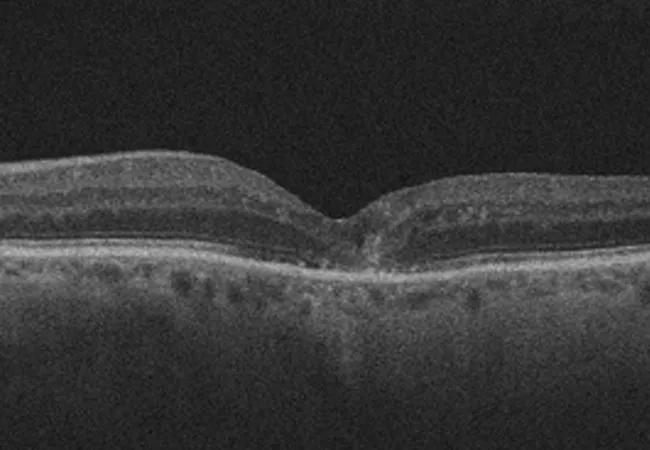

OCT images of a patient with neovascular age-related macular degeneration at baseline (A),

post-lapse (B) and 12 months after restarting anti-VEGF treatment (C). OCT images of a patient with diabetic macular edema at baseline (D), post-lapse (E) and 12 months after

restarting anti-VEGF treatment (F).

In the nAMD study, the average treatment lapse was 5.0 ± 3.7 months. In contrast to the DME study, nAMD patients in the lapse group experienced significant increases in central subfield thickness that normalized upon resumption of treatment, as well as concordant decreases in visual acuity that trended downward over time despite the normalization of central subfield thickness. Visual acuity in the lapse group was significantly lower when compared to the control group at all time points following the lapse (-6.62 letters at post-lapse [P < 0.01], -6.59 letters at three months [P < 0.01], -6.16 letters at six months [P < 0.01] and -5.46 letters at 12 months [P < 0.01]). In contrast, the control group’s central subfield thickness and visual acuity remained relatively constant throughout the study period.

These findings demonstrate that, despite the efficacy of anti-VEGF treatment in resolving gross anatomical derangements, the damage done to the retina on a cellular level and the deterioration of visual acuity after a lapse may, in many instances, be irreversible and is dependent on the disease being treated. Taken together, information from these studies informs providers of the visual loss that can occur with lapses and allows providers to better counsel patients on the consequences of LTFU.